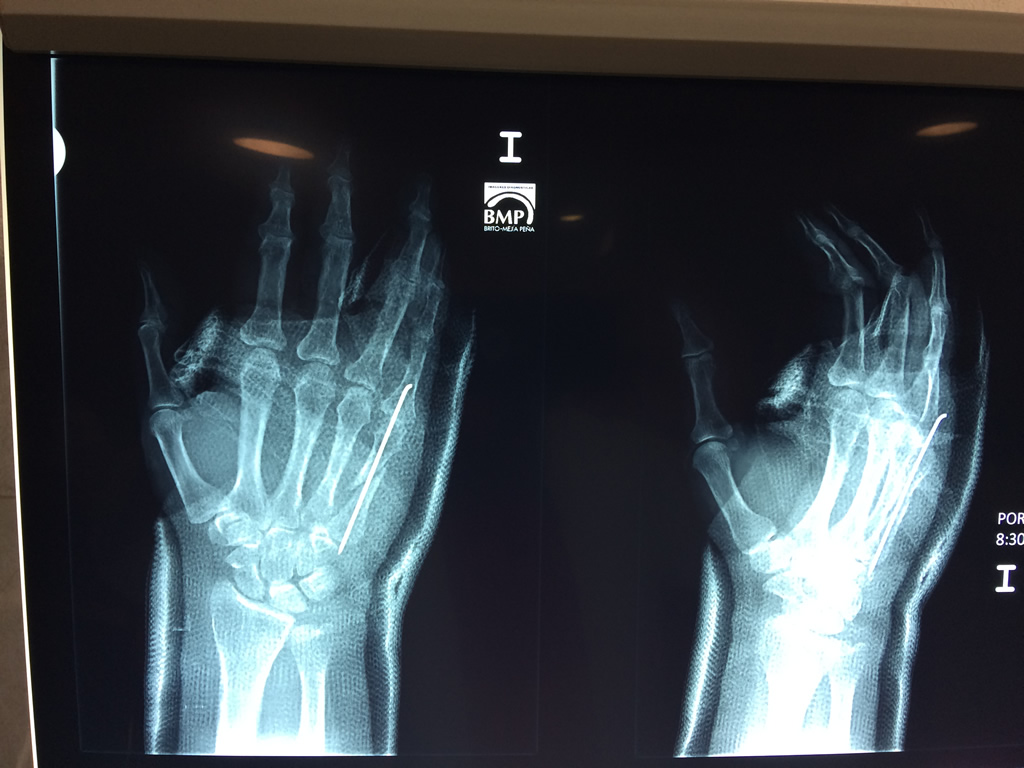

Cirugía de Muñeca y Mano

Los procedimientos más comunes en cirugía de la mano son aquellos destinados a reparar traumatismos, incluyendo lesiones de tendones, nervios, vasos sanguíneos, y articulaciones; huesos fracturados; y quemaduras, cortes, y otros daños de la piel.